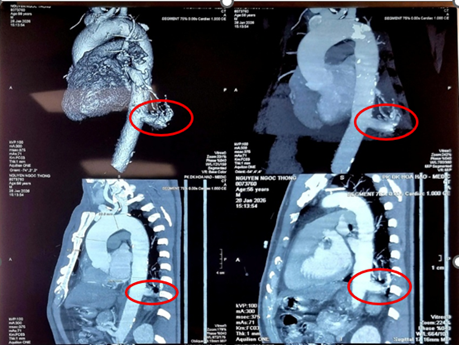

Tại Bệnh viện Bình Dân, các bác sĩ chẩn đoán ông mắc phổi biệt lập nội thùy với khối kích thước 23 mm × 26 mm. Đáng chú ý, động mạch nuôi khối này xuất phát trực tiếp từ động mạch chủ xuống với đường kính lên tới 17 mm – một kích thước rất lớn và đầy rủi ro nếu người bệnh không được điều trị.

Hình MSCT ngực của người bệnh. Ảnh: BVCC

ThS.BSCKII. Nguyễn Văn Việt Thành – Trưởng khoa Ngoại Lồng ngực – Bướu cổ, Bệnh viện Bình Dân cho biết, khó khăn lớn nhất là phẫu tích nhánh động mạch nuôi này. Mạch máu này to, dễ vỡ và rất dính do tình trạng nhiễm trùng mạn tính xung quanh. Một sai sót nhỏ cũng có thể dẫn đến biến cố chảy máu không thể kiểm soát.